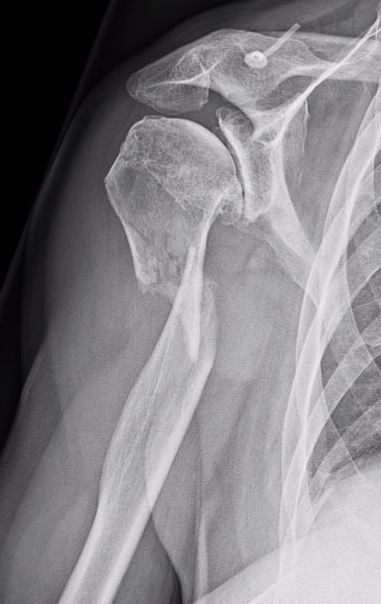

X-ray

1. Punched out lytic lesions

- axial and appendical skeleton

- widely disseminated

- soap bubble appearance

- no sclerotic reaction

3. Vertebrae Plana

4. Pathological Fracture